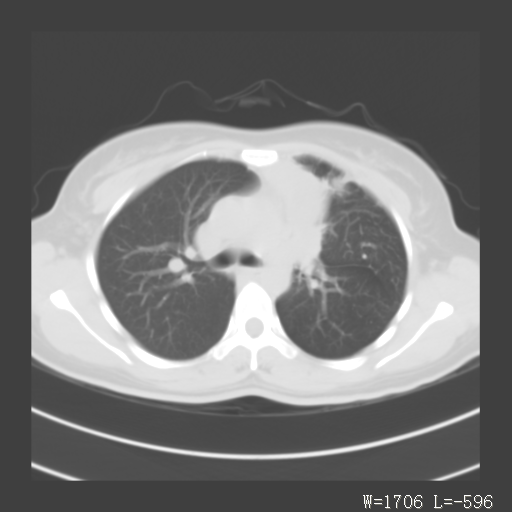

1)考虑左肺上叶肺脓肿,节段性肺不张。2)永存左上腔静脉。

1)考虑左肺上叶节段性肺不张。原因?2)永存左上腔静脉。

考虑左肺上叶胸腺瘤可能性大。肺不张/永存左上腔静脉

胸骨后偏左侧囊实性病灶,考虑胸腺瘤可能性大.

1、胸骨后偏左侧囊实性病灶,考虑胸腺瘤可能性大。2、永存左上腔静脉。